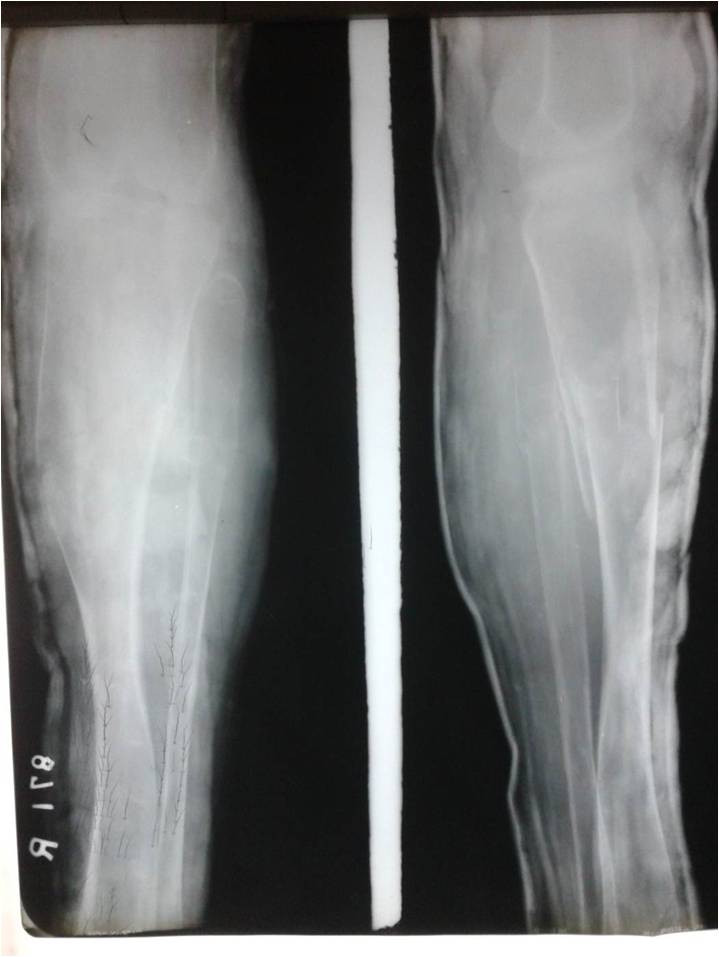

Pyles Dysplasia1